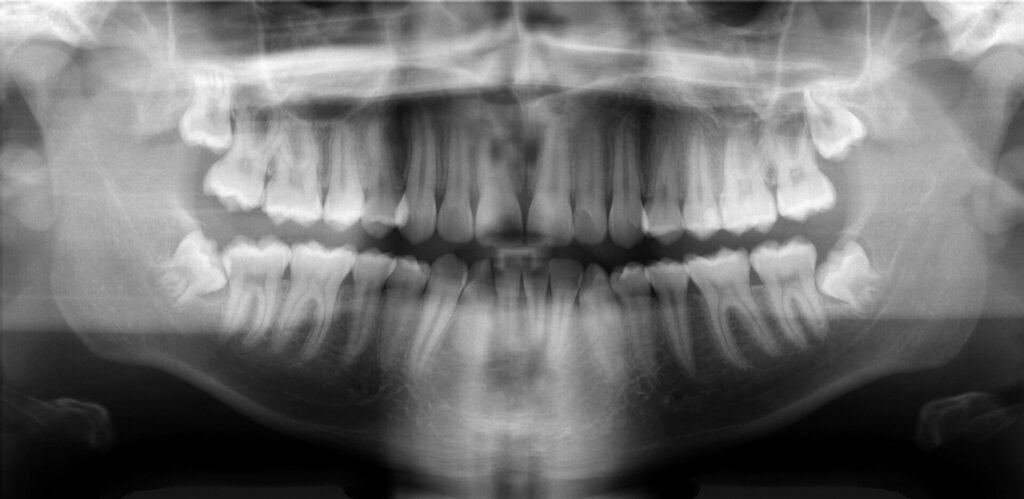

Principios del pasado mes de julio. Al hospital Saveetha Dental College en Chennai, India, llega un pequeño de siete años con dolores y gran hinchazón en la mandíbula inferior derecha. Cuando termina la jornada los doctores no daban crédito. Le habían extraído al niño más de 500 dientes de la boca. Según afirmó a los…